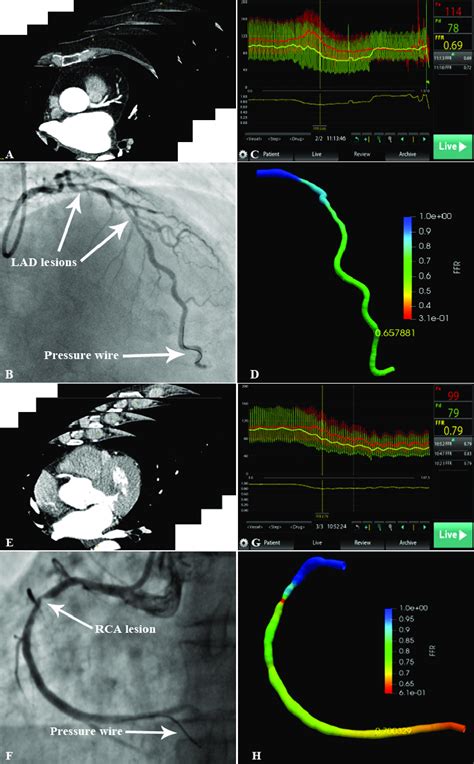

Curious about the magic behind the FFR-CT scan? Let’s walk through it. It all starts with a special type of CT scan called a coronary CT angiography (CCTA) . This isn’t your average chest X-ray, guys. You’ll likely be given a contrast dye through an IV, which helps highlight your coronary arteries on the scan. The CT scanner takes incredibly detailed, rapid images of your heart as it beats. Think of it as taking thousands of high-speed photos from every angle. Once we have these high-resolution images, the real wizardry begins. The CCTA data is then sent to specialized software. This isn’t just any software; it’s powered by complex algorithms and computational fluid dynamics (CFD) . CFD is a branch of physics that uses mathematical equations to simulate how fluids – in this case, blood – move and behave. The software takes the 3D anatomical information from your CT scan and essentially builds a virtual replica of your coronary arteries. It then simulates the blood flow through these arteries, taking into account factors like the shape and severity of any narrowings, the heart’s pumping action, and even the resistance in the smaller blood vessels downstream. By analyzing the pressure and flow rates at different points in the arteries, the software can calculate the FFR value for any given point. An FFR value of 1.0 means there’s no pressure drop, indicating normal flow. As the FFR value decreases (e.g., below 0.80), it signifies a significant blockage that’s impeding blood flow. This entire process is done virtually, on a computer, using the data from your scan. So, you lie down for a CT scan, and the FFR calculation happens later, in the digital realm. It’s a fantastic example of how advanced computing and medical imaging are coming together to provide deeper insights into our health.